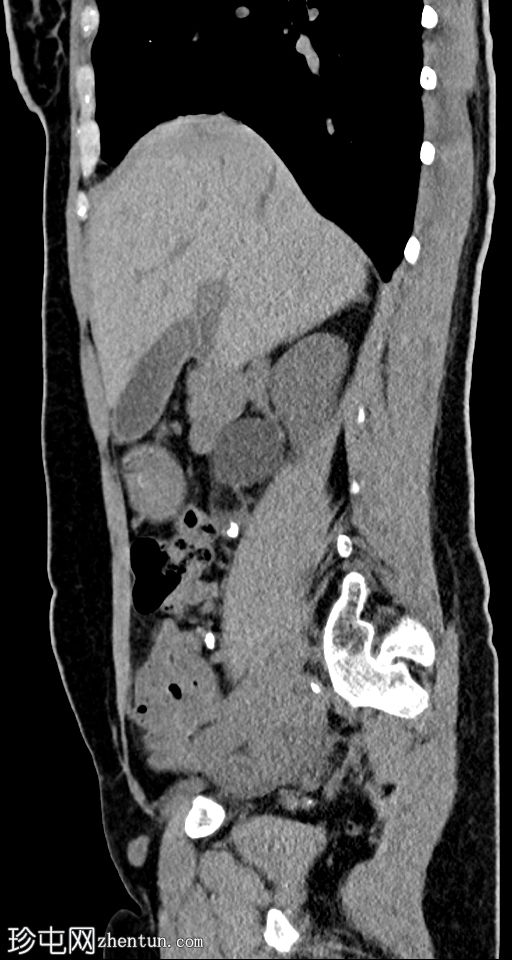

矢状位

平扫

右侧输尿管上段可见一小块高密度结石(约1500 HU)

近端输尿管及右侧肾盂肾盏系统中度扩张

右髂窝内可见多个小钙化结节,符合钙化淋巴结的特征